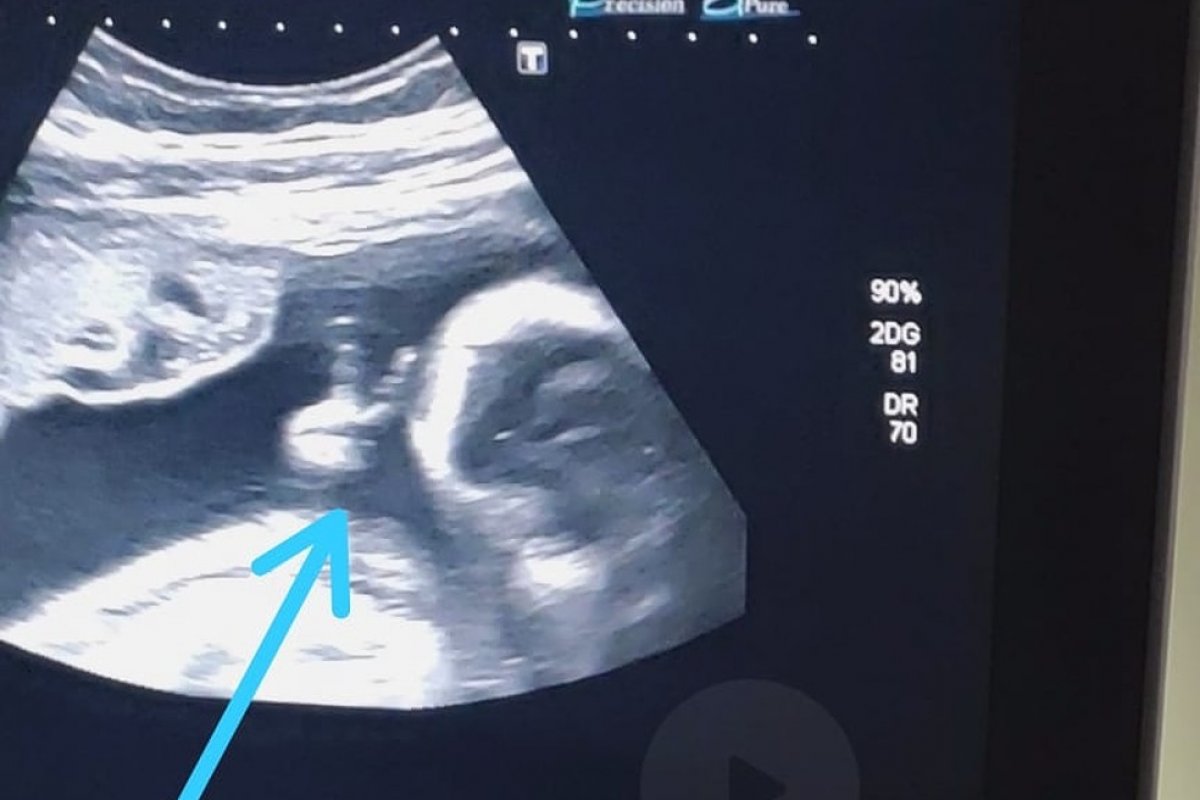

Durante o acompanhamento do exame de ultrassonografia de sexto mês do primeiro filho, Felipe Moreira dos Santos, de 32 anos, teve uma surpresa: o bebê fez um "V de vitória" com a mão, dentro do útero da mãe. O rapaz, que enfrenta um câncer raro no baço, viu o sinal como mensagem divina.

O rapaz contou ao G1 que ao ver a ultrassom ficou bastante emocionado, porque conseguiu observar o desenvolvimento do bebê e ouvir o coraçãozinho. Ao ver o filho Davi fazendo o sinal do V com uma das mãos, ficou sem acreditar. “O filho que eu pedi para Deus foi para superar tudo isso que estou passando. Esse sinal foi para fechar com chave de ouro, para eu ter certeza que vou vencer. Se não tivesse ido, não teria visto isso, porque minha mulher não ia conseguir gravar. Aí, eu vou para o ultrassom e tem um sinal desse, parece que é para a minha fé aumentar. Me dá mais força para poder vencer o câncer. Com certeza, foi um sinal divino”, finaliza.